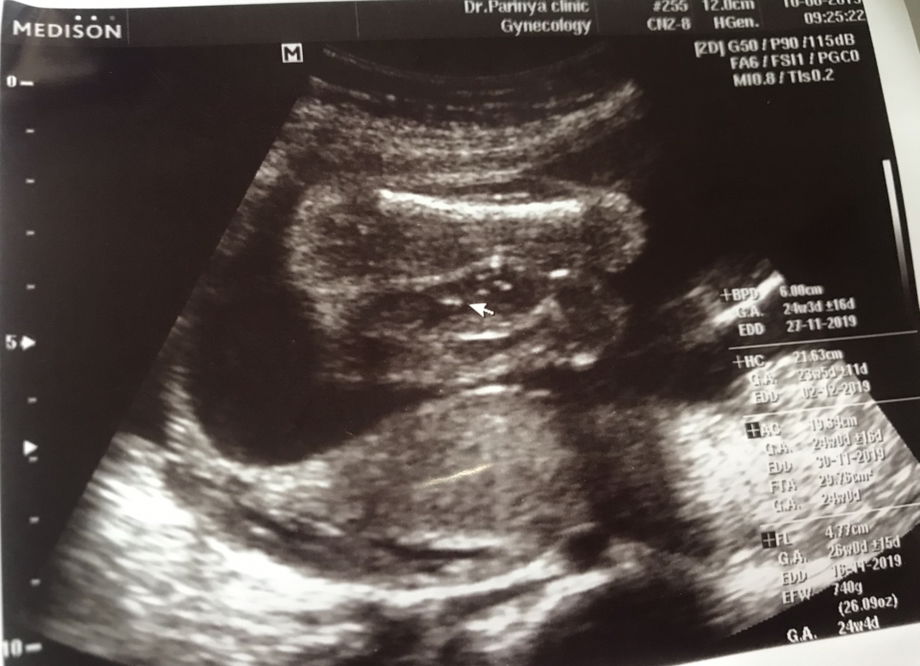

แชร์รูปกันหน่อย

แม่ๆช่วยแชร์รูปอัลตราซาวด์เพศของลูกหน่อยค่ะ ของแม่ชายครับ

ชายหรือหญิงคะ

ช่วยดูหน่อยค่ะที่ยื่นออกมานั้นคือจู๋ใช่มั้ยคะ 20 วีคค่ะ หมอบอกผู้ชาย แต่คนแรกก็ผู้ชาย ลักษณะไม่เหมือนของคนแรกค่ะเลยไม่แน่ใจ ขอแม่ๆแต่ละคนเป็นแบบไหนกันบ้างคะ ขอดูหน่อยค่ะ

ชายหรือหญิงค่ะ

ช่วยดูหน่อยค่ะที่ยื่นออกมานั้นคือจู๋ใช่มั้ยคะ 20 วีคค่ะ หมอบอกผู้ชาย แต่คนแรกก็ผู้ชาย ลักษณะไม่เหมือนของคนแรกค่ะเลยไม่แน่ใจ

เพศหญิงกับเพศชาย

พอดีกำลังจะไปหาหมออัลตราซาวด์ดูเพศค่ะ ท้องได้20สัปดาห์แล้ว อยากจะขอดูรูปอัลตราซาวด์ที่บอกเพศได้ ของเพื่อนหน่อยค่ะ